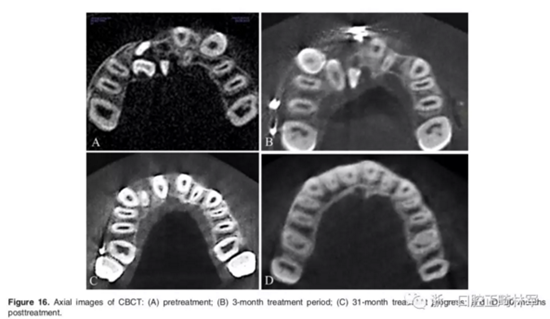

影像學(xué):頭顱側(cè)位片示:矢狀向和垂直向骨骼發(fā)生變化(ANB角,3°;SN-MP,51°);上頜切牙略前傾(U1-SN,106°),與下頜切牙一致(IMPA,75°);病人的面部輪廓得以保持。全景片示:由于牙齒萌出,上前牙區(qū)垂直向牙槽骨水平增加;雖然前牙牙根較彎曲,但其平行度仍可,且無(wú)明顯的牙根吸收。CBCT示:前牙唇側(cè)骨質(zhì)連續(xù)性改善,牙根唇側(cè)支持組織變好,牙槽骨高度、厚度均有增加,但轉(zhuǎn)矩的改變一定程度上導(dǎo)致了局部應(yīng)力的增大。

2年隨訪:咬合關(guān)系保持穩(wěn)定,無(wú)明顯復(fù)發(fā),下頜有一定晚期生長(zhǎng)趨勢(shì);前牙牙齦外形、牙冠高度無(wú)明顯變化;唇側(cè)牙槽骨高度、厚度均保持良好。